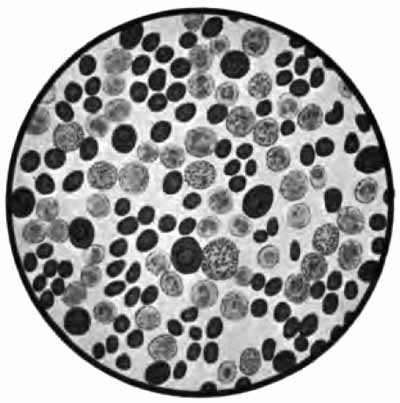

In films stained by Gabbet's method tubercle bacilli, if present, will be seen as slender red rods upon a blue background of mucus and cells (Plate II, Fig. 2). They average 3 to 4 µ in length—about one-half the diameter of a red blood-corpuscle. Beginners must be warned against mistaking the edges of cells, or particles which have retained the red stain, for bacilli. The appearance of the bacilli is almost always typical, and if there seems room for doubt, the structure in question is probably not a tubercle bacillus. They may lie singly or in groups. They are very frequently bent and often have a beaded appearance. It is possible that the larger, beaded bacilli indicate a less active tuberculous process than do the smaller, uniformly stained ones. Sometimes they are present in great numbers—thousands in a field of the one-twelfth objective. Sometimes several cover-glasses must be examined to find a single bacillus. At times they are so few that none are found in stained smears, and special methods are required to detect them. The number may bear some relation to the severity of the disease, but this relation is by no means constant. The mucoid sputum from an incipient case sometimes contains great numbers, while sputum from large tuberculous cavities at times contains very few. Failure to find them is not conclusive, though their absence is much more significant when the sputum is purulent than when it is mucoid.

PLATE II

Sputum showing tubercle bacilli

FIG. 2.—A, Sputum showing tubercle bacilli stained with carbol-fuchsin and Gabbet's methylene-blue solution (obj. one-twelfth oil-immersion); B, sputum of anthracosis, showing particles of coal-dust stained with methylene-blue (obj. one-twelfth oil-immersion) (Boston).

(2) Staphylococcus and Streptococcus (p. 262).—One or both of these organisms is commonly present in company with the tubercle bacillus in the sputum of advanced phthisis (Plate II, Fig. 2). They are often found in bronchitis, catarrhal pneumonia, and many other conditions.